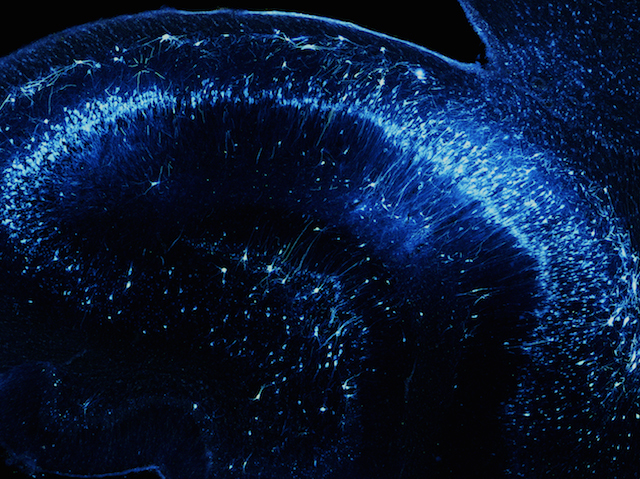

Batten disease is a devastating and ultimately fatal neurodegenerative condition that generally afflicts young children. Previously healthy kids begin to suffer impaired vision, behavioural changes, learning difficulties, and often seizures. A decline in motor skills follows and eventually the children, who often don’t reach their tenth birthdays, become completely reliant on their carers. Thankfully Batten disease, which can be caused by mutations to the TPP1 gene, is extremely rare. However, this also means the condition doesn't receive the sort of research interest and funding as, say, cancer or heart disease. Nevertheless progress is being made, and this Rare Disease Day we celebrate a recent gene-therapy breakthrough achieved in dogs with the disease. The brain slice pictured is from a dog treated with the therapy and shows the gene’s product, TPP1 (blue), inside neurons. Therapy both extended life-span and improved cognition in the dogs, offering hope for future human trials.